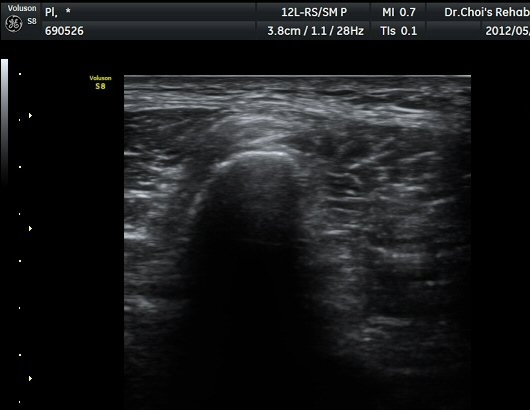

ŽÃËÀÚ¸¦ ¾Æ·¡·Î À̵¿ÇÏ¿© ºñ°ñµÎ ºÎÀ§±îÁö ÃѺñ°ñ½Å°æÀÇ ÁÖÇàÀ» µû¶ó ½Å°æÀ» È®ÀÎÇÏ¿´´Ù(±×¸² 3, 4).